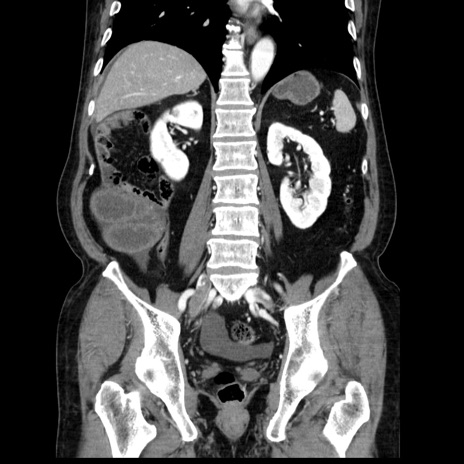

症例30(冠状断像)

【症例】80歳代男性

【主訴】臍周囲痛

【現病歴】約6時間前から臍下部痛が出現。次第に腹部膨隆・背部痛も生じてきたため来院。背部痛の場所は変化しない。

【身体所見】意識清明、BT 36.3℃、BP  131/87mmHg、P 87bpm、SpO2 100%(RA)、臍周囲自発痛・圧痛あり、反跳痛なし、自発痛部位に一致して板状硬あり、腹部膨隆、腸雑音減弱、CVA tenderness両側陰性。

【データ】WBC 19600、CRP 0.33

横断像